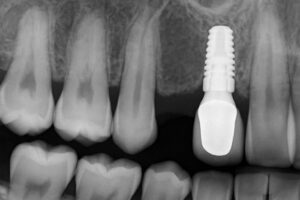

X‑rays reveal bone loss around the tooth root, root fractures, or other hidden problems. Periodontal charting measures pocket depths and gum attachment levels. Together, these records show whether gum disease or bone loss is causing the mobility.

Tooth replacement choices

After extraction, options include bridges, removable dentures, or dental implants to restore function and prevent shifting.